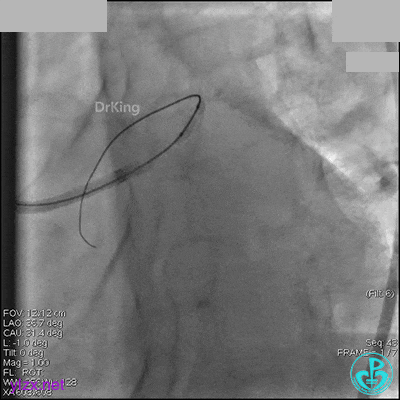

冠脉造影

入院次日冠脉造影显示粗大左主干末端中度狭窄,前降支开口严重狭窄,回旋支与前降支角度大,弥漫性长病变,严重狭窄,粗大右冠脉近中段弥漫性中重度狭窄。由于病变复杂,造影结束后先下台,择期再行介入治疗。